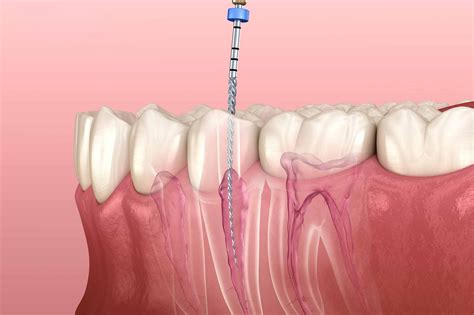

2. Accessing the Pulp: A small hole is made in the crown of the tooth to gain access to the pulp chamber and the root canals.

3. Cleaning and Shaping: The infected pulp is carefully removed using specialized dental instruments. The canals are then cleaned, disinfected, and shaped to receive a filling material.

4. Filling and Sealing: The hollowed-out canals are filled with a biocompatible material called gutta-percha, which is cemented into place.